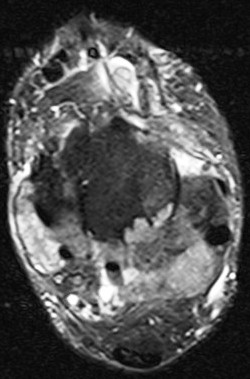

54 y/o with pain and soft tidssue masses of both feet

Gout arthritis ( RID3567 )

Even infiltrating his Tibialis Anterior.